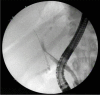

COVID Bile Duct: Biliary Cast Syndrome as a Complication of SARS-CoV-2 Infection